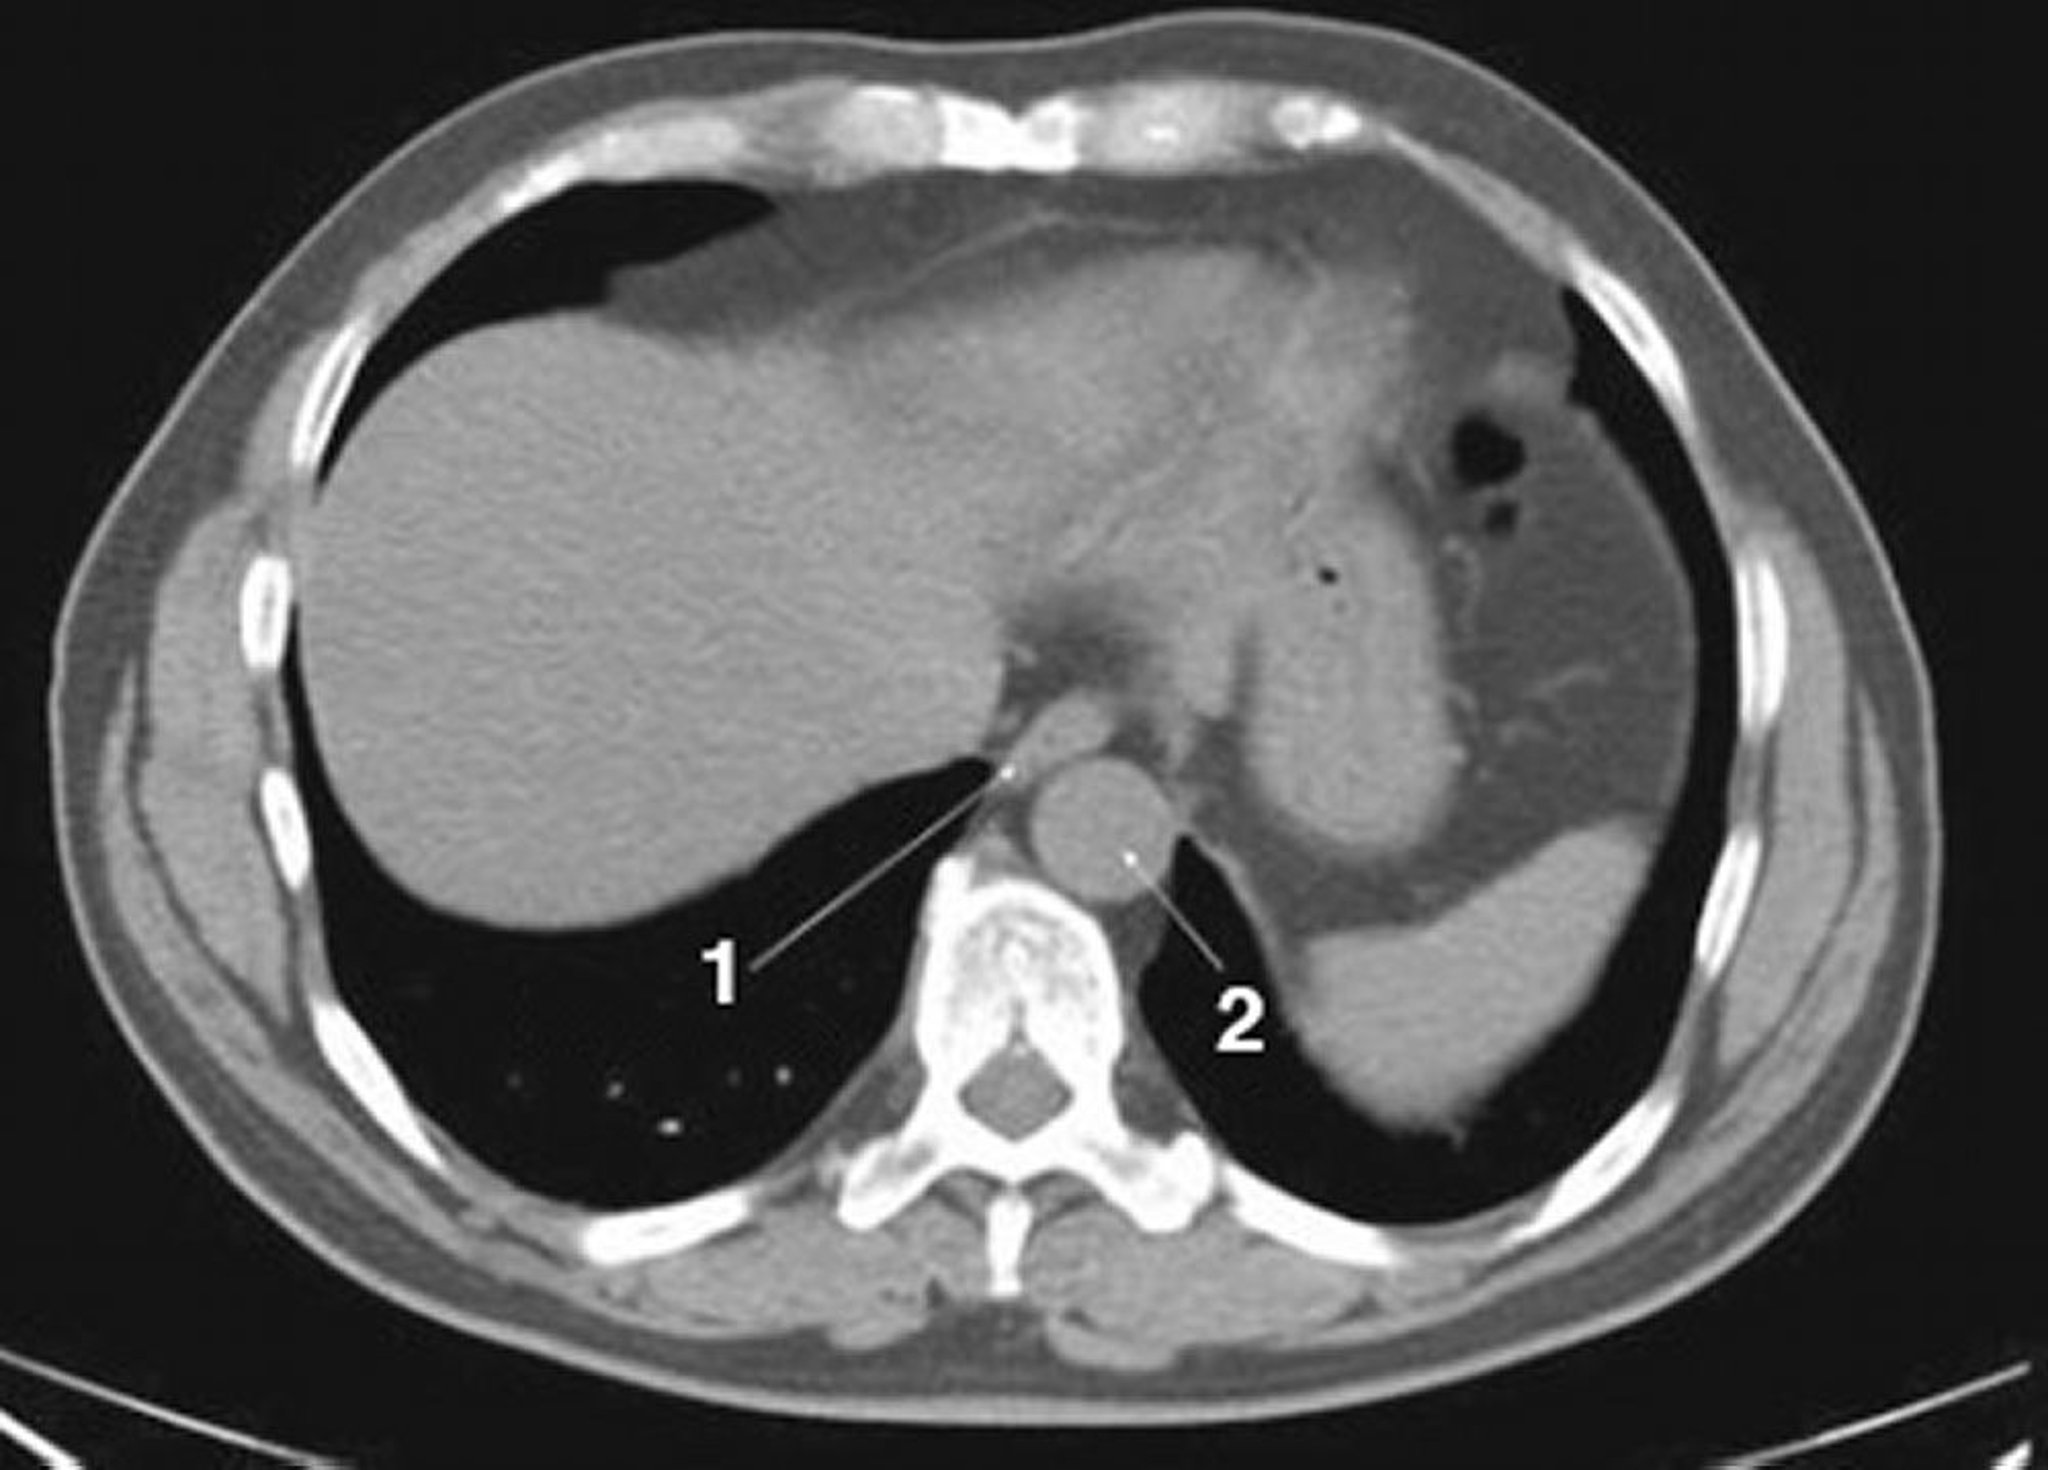

Noncontrast CT Scan of the Abdomen and Pelvis Showing Normal Anatomy (Slide 1)

1 = esophagus; 2 = aorta.